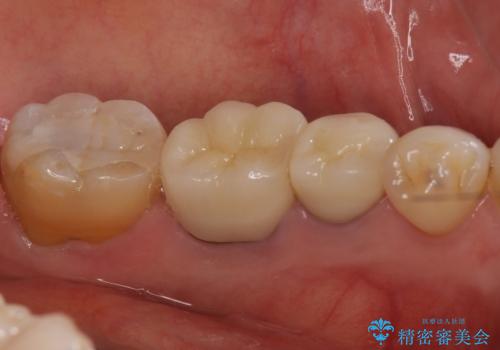

左下5番は根管治療のやりなおし、左下6番は上物(クラウン)のやり替えのみを行いました。

左下7番はアマルガムが入っていたため、ご希望によりセラミックインレーで治療を行っています。

- 44万円(内訳 左下7:emaxプレスインレー 左下6:仮歯、ジルコニアクラウン 左下5:精密根管治療再治療、ファイバーコア、仮歯、ジルコニアクラウン)費用は治療当時の料金となります